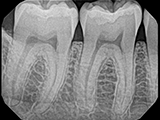

| X-Ray Example |

X-ray taken with the Pro Sensor |

X-ray taken with the Dream Sensor |

X-ray taken with the Open Sensor |

X-ray taken with the Dexis Sensor |

X-ray taken with the Schick 33 Sensor |

X-ray taken with the Carestream Sensor |